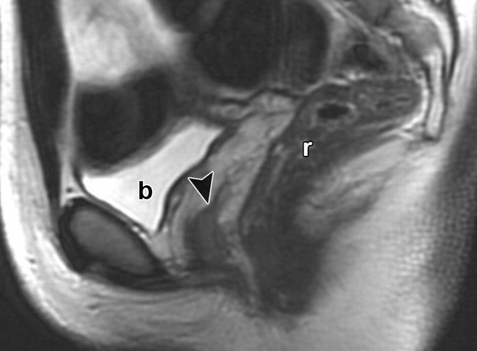

Bicorne VS Septé